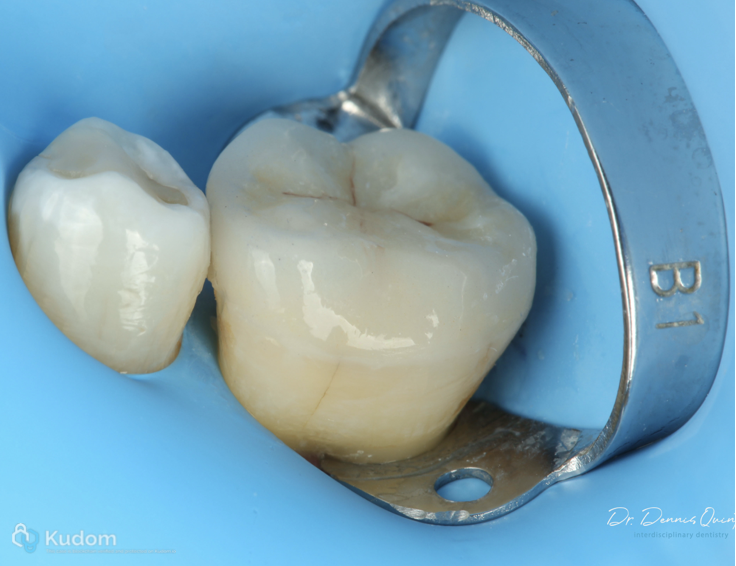

Endo treatment, build up & partial adhesive prep.

Fig. 16

Appointment for cementation.

Conservative overlay preparation.

Material emax.